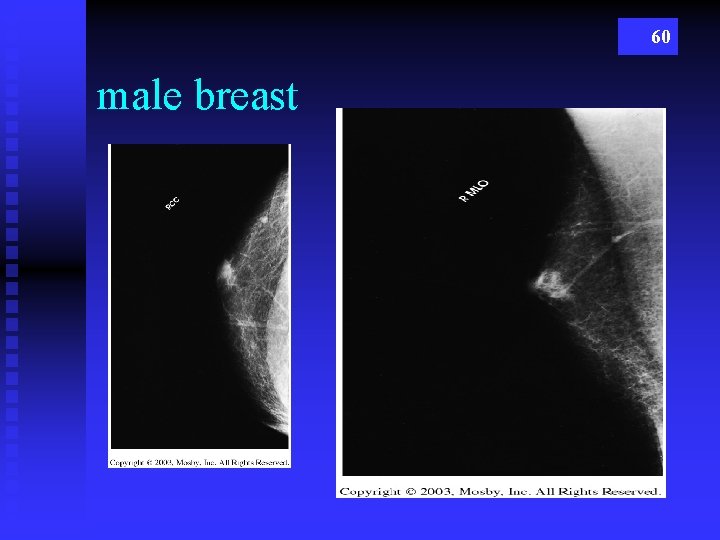

60 male breast